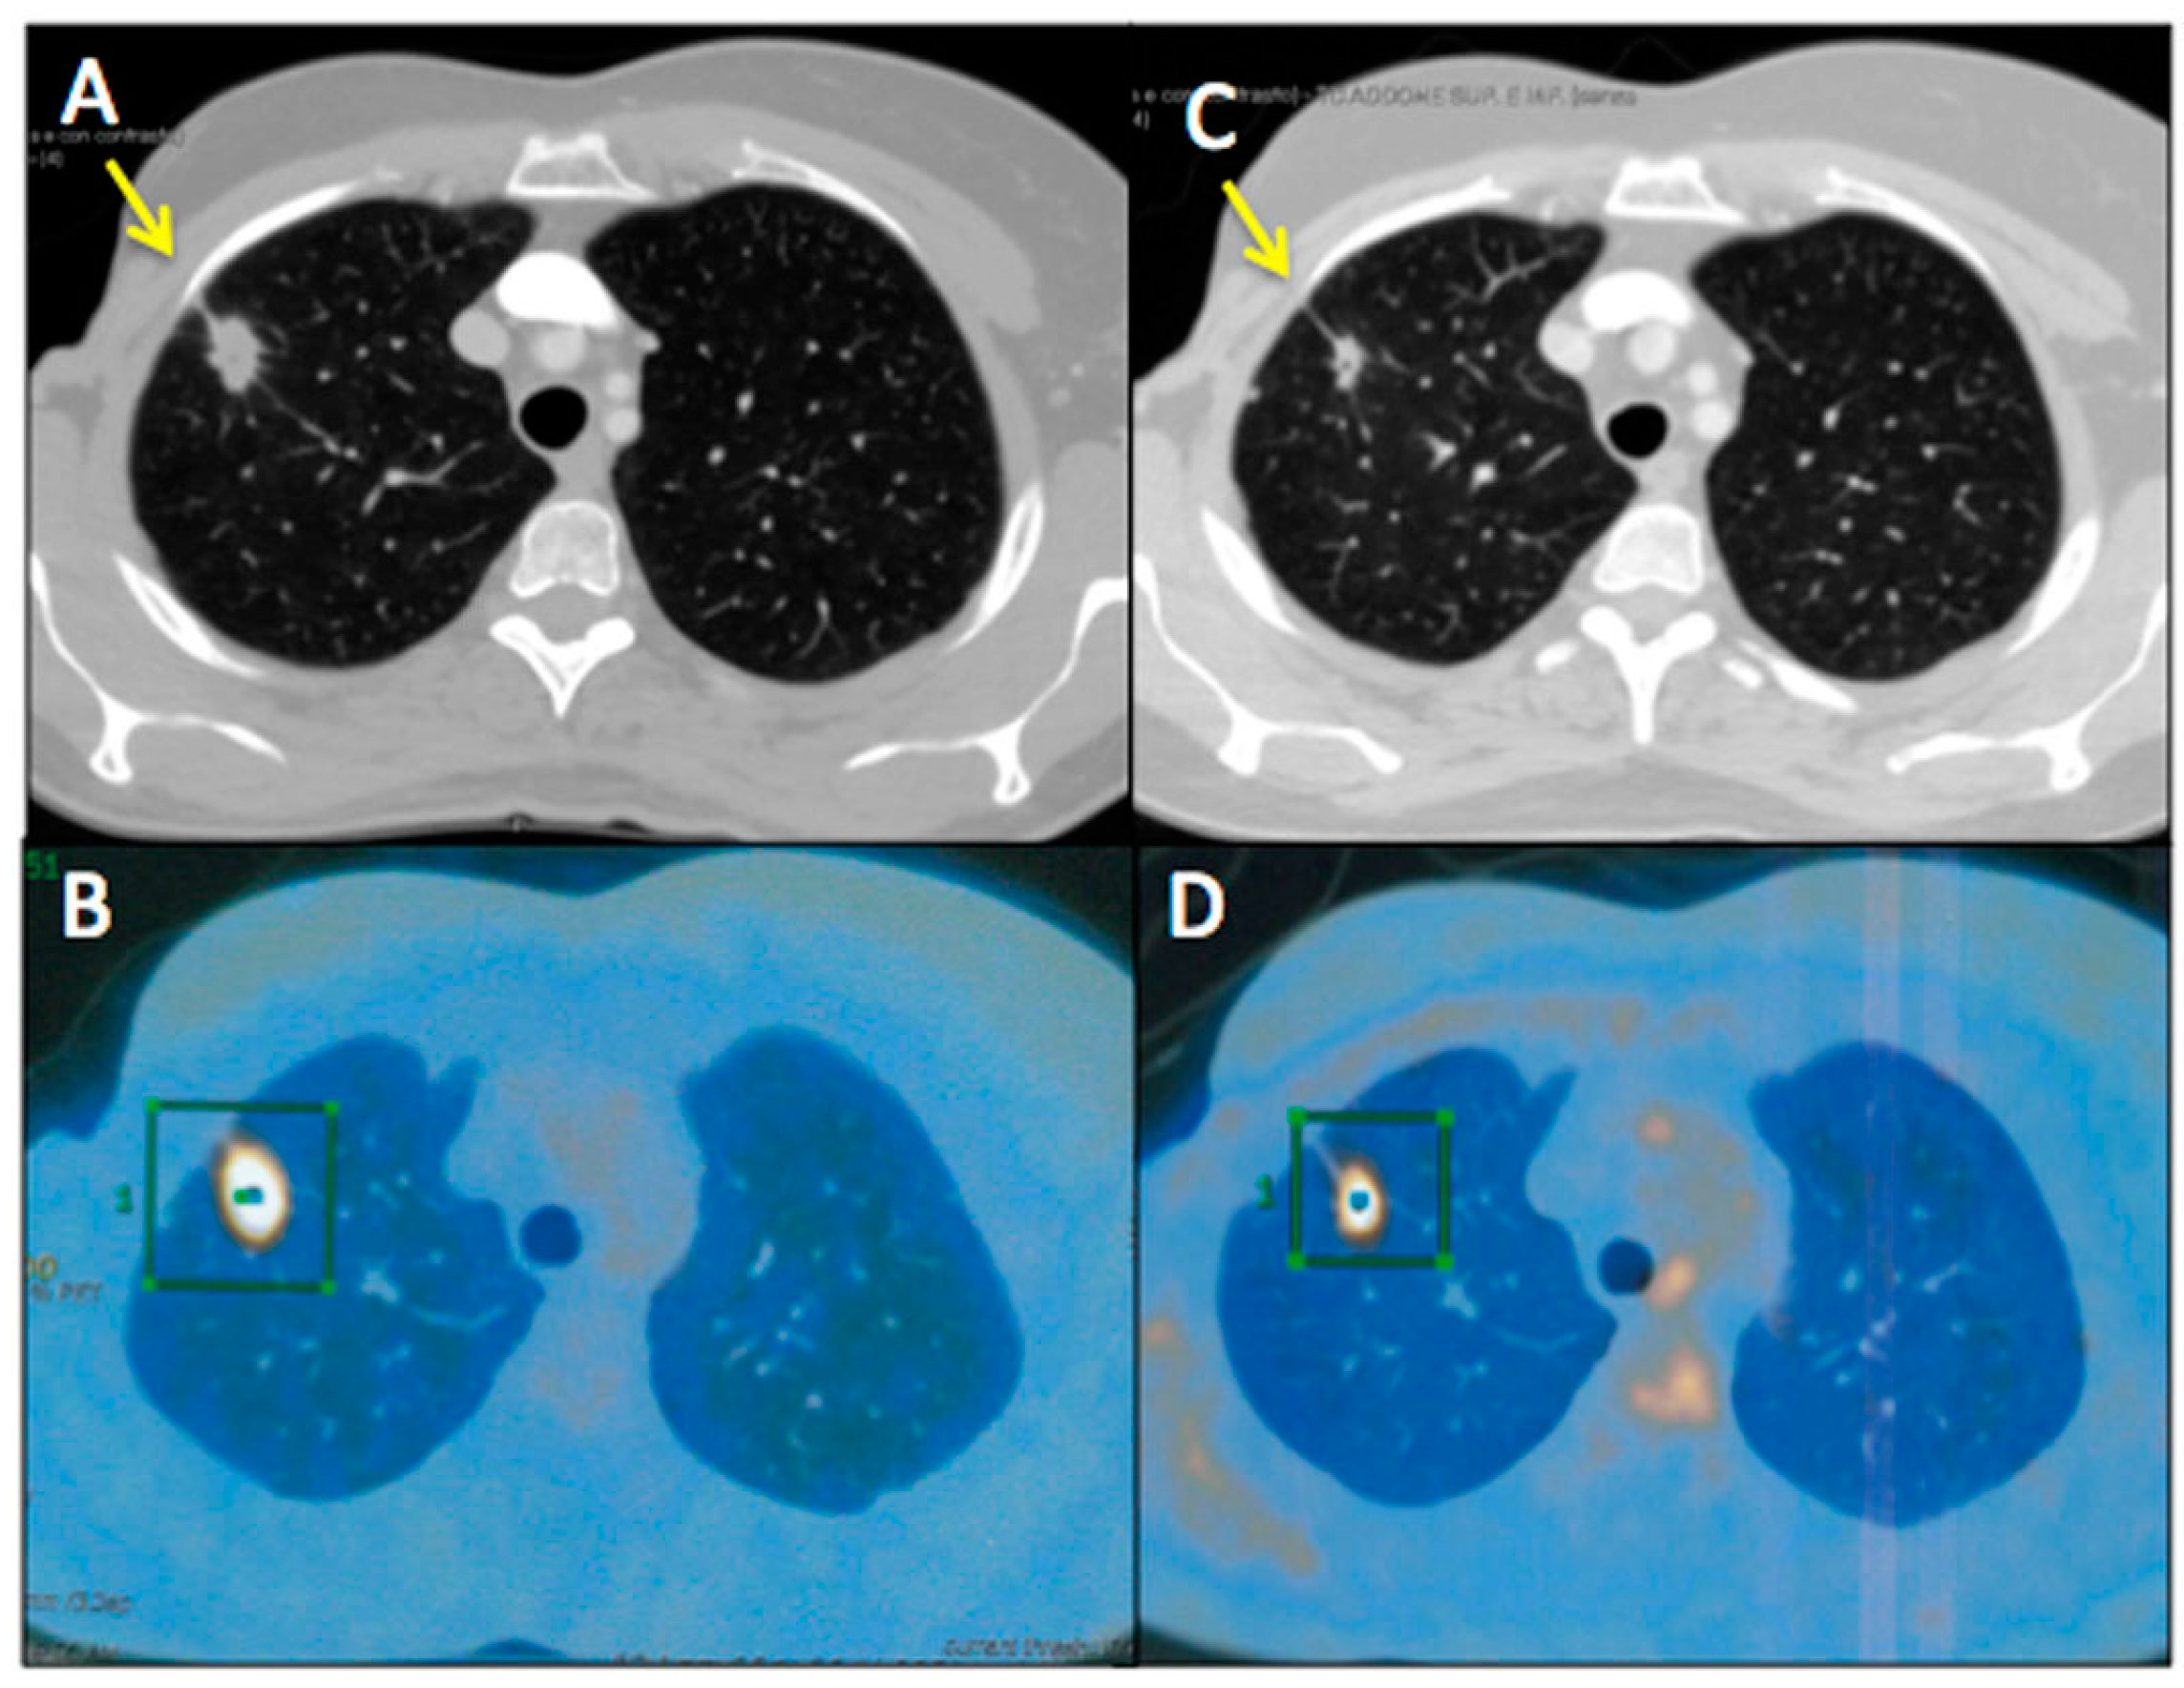

Figure 3 and Figure 4 represent two exemplar cases of patients judged to be PR and CR, respectively, at timepoint-2 evaluation.

Figure 4. A56-year-old female affected by ovarian cancer with liver and spleen metastasis, already treated with 12 cycles of Bevacizumab-based chemotherapy and 24 hyperthermia sessions on the abdomen, as first-line. Baseline MDCT (C) showed metastasis in III and IV segment of the liver (maximum diameter: 77 mm, green squares) and in the upper spleen (maximum diameter: 61 mm, green square). Baseline whole body 18F-FDG PET/CT (A) confirmed liver and spleen involvement by the increased 18F-FDG uptake (yellow arrows) detectable also on axial fused PET/CT images (B) in the same sites (green and red squares). Timepoint-2 MDCT (D) evaluation demonstrated significant size decrease of liver and spleen metastasis (yellow squares) with no evidence of 18F-FDG uptake on whole body PET/CT (E). According to mRECIST, patient was classified as CR. Ca125 value evaluated at baseline was 790 UI/mL; while Ca125 value evaluated at timepoint-2 was 12 UI/mL. Side effects reported were limited to asthenia and high blood pressure.